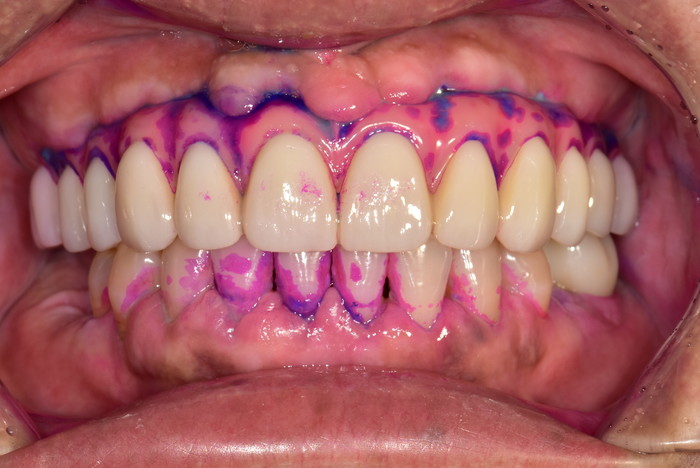

입안사진

치면착색검사